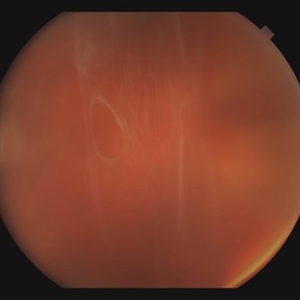

Extra Macular CNV

Aug 24 2012 by John S. King, MD

P/C c mild VFD

Photographer: Kristin Konecki, OcuSight Eye Care Center, Rochester, NY

Extra Macular CNV with Spontaneous Resolution

Spontaneous resolution at the 4-month visit.

Condition/keywords: choroidal neovascularization (CNV), spontaneous resolution